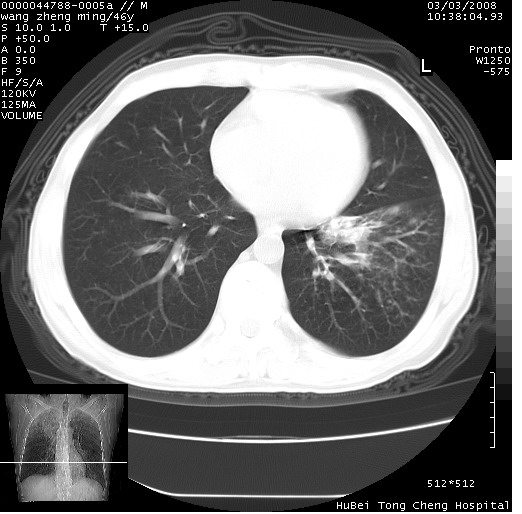

以下是引用卜一在2008-3-22 1:37:00的发言:[br]右肺实质性肿块,边缘不整,明显见毛刺征 分叶征及胸膜凹陷征,右上叶支气管明显变窄,远端散在的片状 斑片状实变影。另:左肺门较大肿块,支气管受累 变窄,远侧见阻塞性肺炎。纵隔内见肿大淋巴结。多考虑:右肺周围性肺癌伴左肺门 纵隔淋巴结转移!